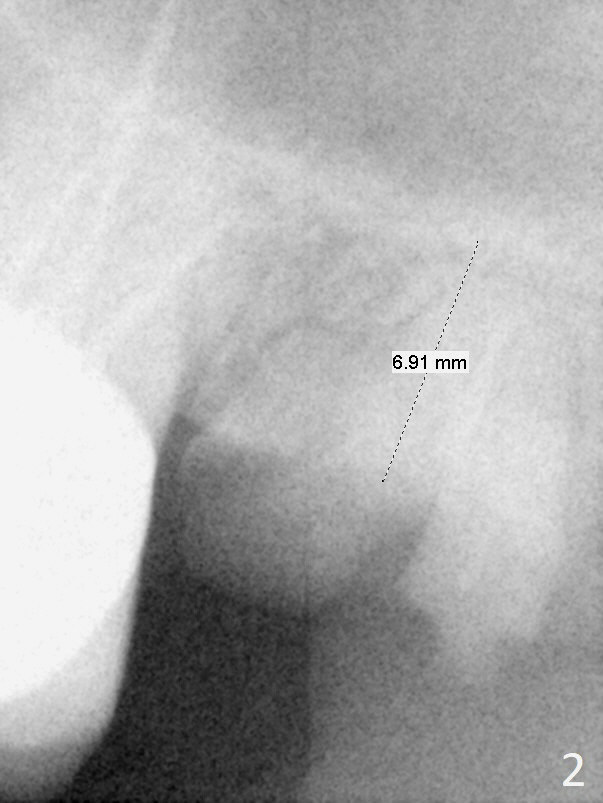

A 47-year-old woman has residual roots at #15 and 19 (Fig.1). Seven years earlier, the bone height is ~ 7 mm (Fig.2), as compared to ~5 mm now (Fig.3). It is apparent that the bone height decreases as the residual roots are expelled. An advantage is that the ridge is flat, easy to initiate osteotomy. Magic Sinus Lifter is to be used for sinus lift. The regular surgical kit should be also available. Proximators will be used to remove the residual roots. Magic Split may be used to initiate osteotomy.